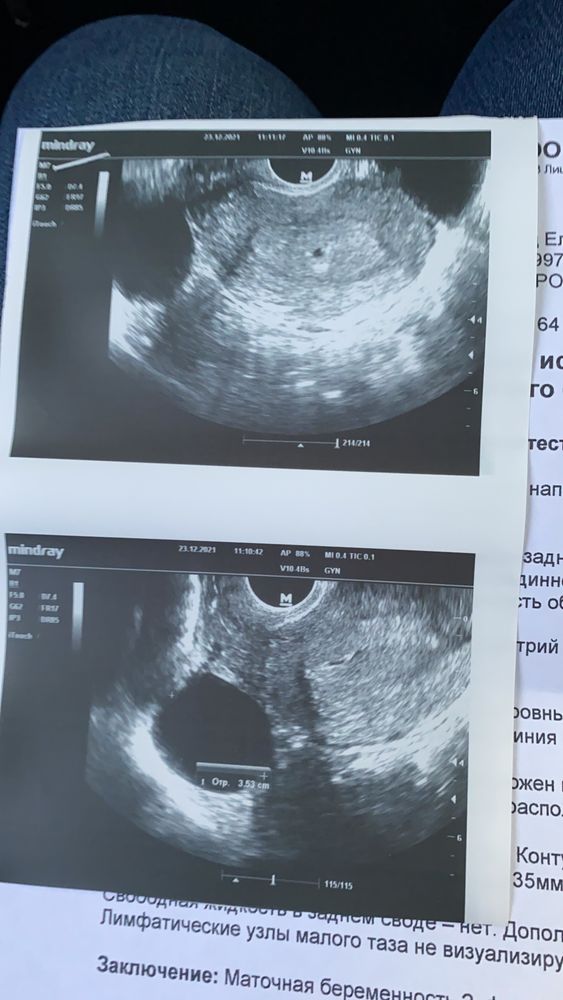

Светлана Сопчинская, Изображение Ещё проблема в том, что есть киста, но безобидная ( на втором снимке). На первом то самое пятнышко

23.12.2021